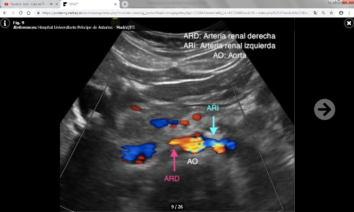

Hay dos grupos de parámetros: Directos o indirectos según se valoren en las arterias renales principales o ramas intrarrenales respectivamente.

Los parámetros directos son más fiables y reproducibles que los indirectos, y son los siguientes:

- Velocidad picosistólica (VPS) : Normal por debajo de 180-200 cm/s.

- Índice reno-aórtico (cociente entre la VPS de la arteria renal y la aorta): Normal por debajo de 3.5-3.6.

- Índice reno-renal (cociente entre la VPS en el punto de estenosis y en un punto distal a la misma): Normal por debajo de 4.